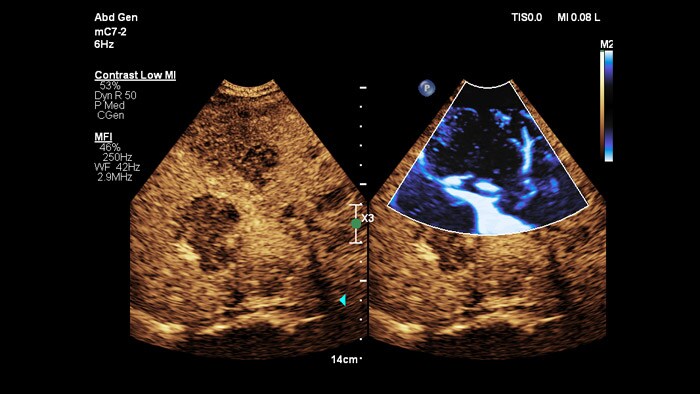

EPIQ Elite LFQ imaging

A universal platform for liver ultrasound

Super Resolution MVI offers an improvement of more than 200% in spatial resolution for EPIQ Contrast-enhanced Ultrasound.2

Philips offers a comprehensive ultrasound solution to support the assessment, treatment and monitoring of liver disease. Four of our key innovations – PureWave, ElastQ and LFQ, Fusion and Navigation – combine for the ultimate liver ultrasound solution.

• Liver Flow Viewer

Portal vein and hepatic artery